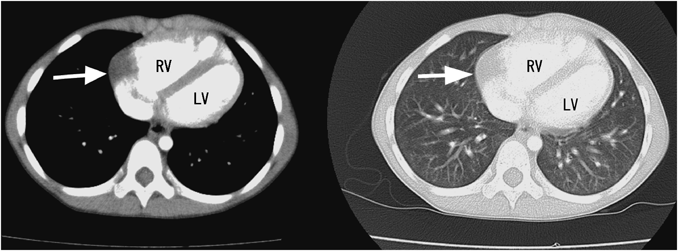

Fig. 1 Transthoracic echocardiography

A: An anechoic lesion (arrow) is located outside of the right atrium (RA) with a clear border in the apical four-chamber view. B: Microbubbles injected from the inferior vena cava fill the chambers, but do not flow into the lesion. RA, right atrium; RV, right ventricle; LA, left atrium; LV, left ventricle

The presence of a cyst was finally confirmed using microbubble echocardiography; this study was added to preplanned cardiac catheterization to evaluate pulmonary arterial hypertension. In this test, the contrast agent injected from the inferior vena cava did not flow into the cavity (Fig. 1B), indicating the lack of communication between the cavity and cardiac structures.

We performed contrast echocardiography to distinguish the cyst from a diverticulum. If the anechoic lesion was a diverticulum, the chamber would be filled with contrast agent, as reported previously.2) Direct injection from the inferior vena cava yielded a vivid image, even with a small amount of contrast medium.